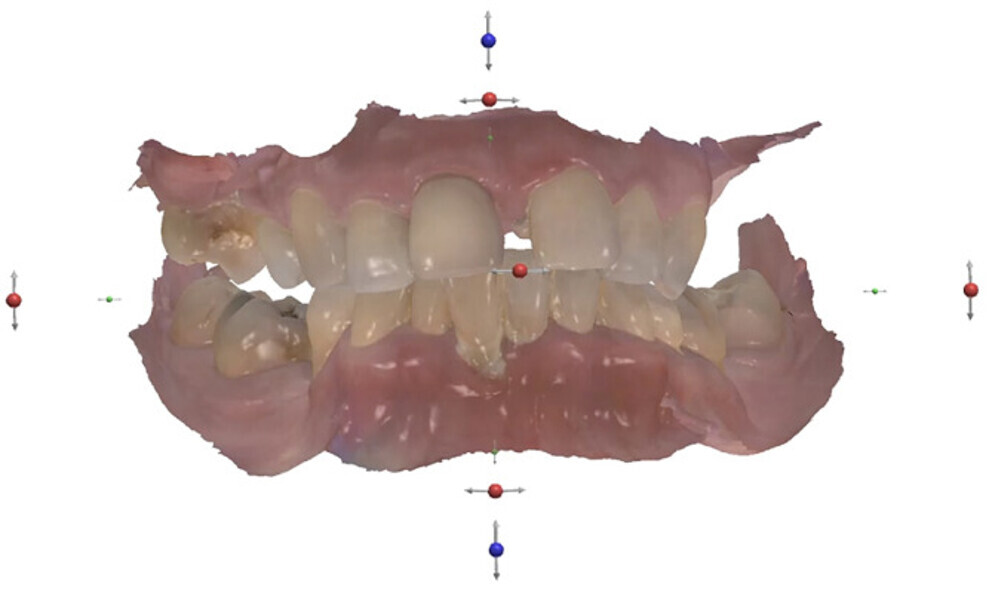

CoDiagnostiX software (Dental Wings) was used for planning the analogue surgical placement of two Straumann zygomatic implants and two Straumann BLX implants in the maxilla and of four Straumann BLX implants in the mandible. The protocol chosen was immediate placement after atraumatic extraction of the remaining teeth while protecting the remaining bone (Figs. 4 & 5). The patient’s STL file was generated and sent to the in-house laboratory to create a 3D-printed model for the surgical planning, allowing us to obtain a surgical model (Fig. 6).

Before surgery, an intra-oral scanner was employed to acquire the digital data for the design of the temporary prostheses (Fig. 7). The teeth were digitally removed, and digital prostheses were created. The data of the virtually constructed prostheses was subsequently transmitted to a milling machine for the fabrication of monolithic PMMA prostheses.